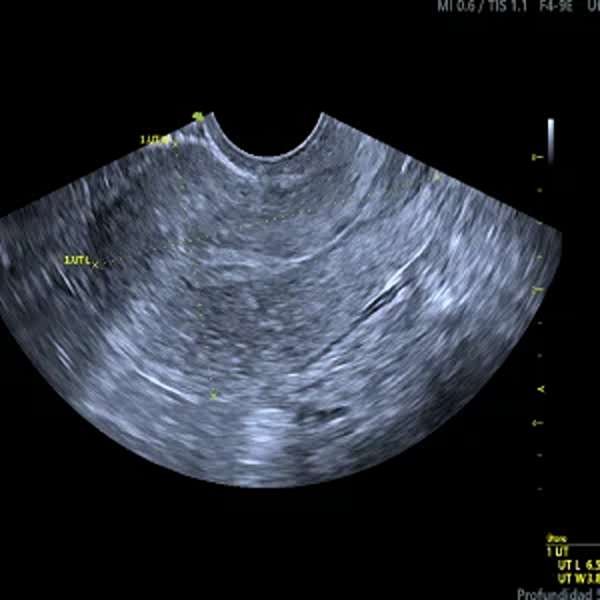

Ecografía Transvaginal

La ecografía transvaginal es un estudio de diagnóstico por imágenes que permite visualizar con alta precisión el útero, los ovarios y el endometrio. Se realiza introduciendo una sonda delgada en la vagina, lo que proporciona imágenes detalladas para detectar quistes, miomas, endometriosis, embarazos ectópicos y otros trastornos ginecológicos. Es un procedimiento seguro, indoloro y rápido, utilizado también en tratamientos de fertilidad y en el control del embarazo temprano. Su precisión lo convierte en una herramienta clave para el diagnóstico y monitoreo de la salud reproductiva femenina.